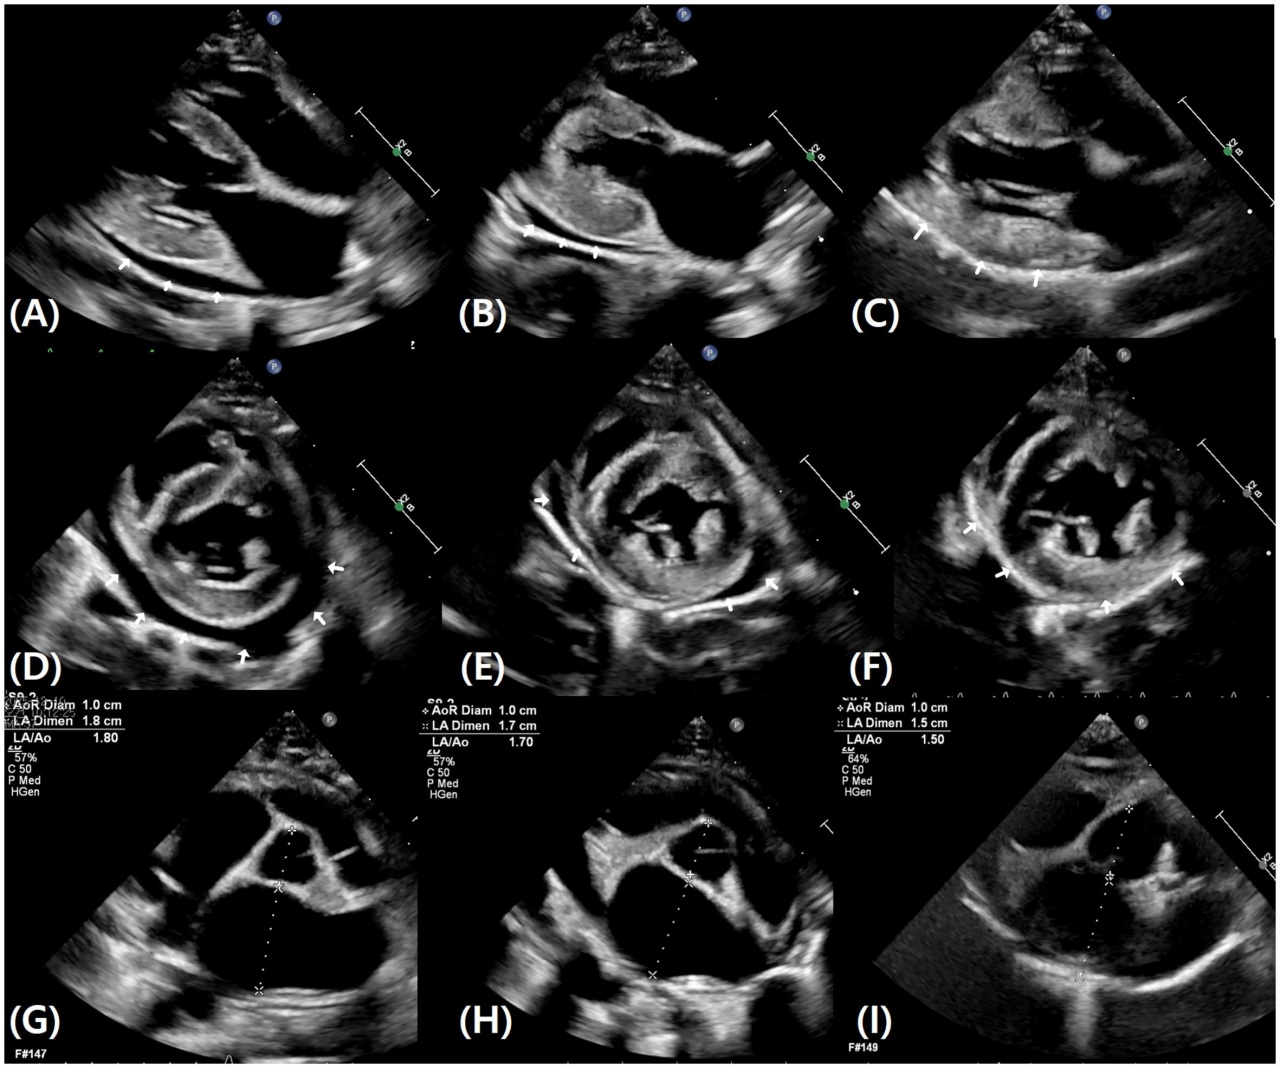

체액 저류로 인한 체중 증가를 의심해 추가 검사를 진행한 결과 흉부 방사선에서는 흉수가, 심초음파에서는 좌심실 비대·좌심방 확장에 동반된 심낭 삼출액이 확인됐다.

그 결과 추적 관찰 기간 동안 흉부 방사선과 심초음파 검사에서 흉수와 심낭 삼출이 점진적으로 감소해 완전히 소실되는 것이 확인됐다. 좌심방 크기 역시 감소하는 경향을 보였다. 루프 이뇨제를 사용하지 않았음에도 울혈이 해소된 것이다.